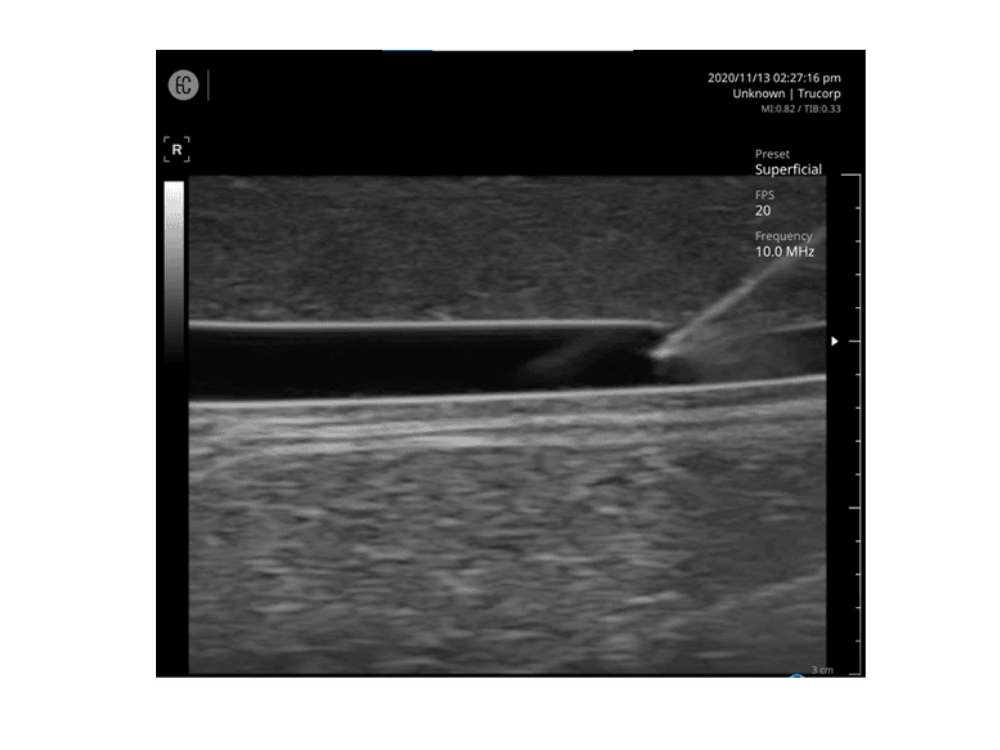

• Målretning af forskellige vener med diametre fra 4 mm til 8 mm. Ultralydsbilleddannelse er ekstremt naturtro.

• Mulighed for både longitudinel og transversal anatomisk visning.

IV-kanylering med ultralydsvejledning

Positionering og bevægelse af probe